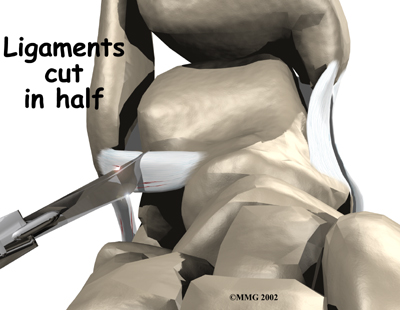

In this procedure, an incision is made in the skin that lies over the lateral ligaments. Using a scalpel, the surgeon cuts the ATFL and CFL in half.

The following images show each step of the ligament tightening procedure:

Step 1